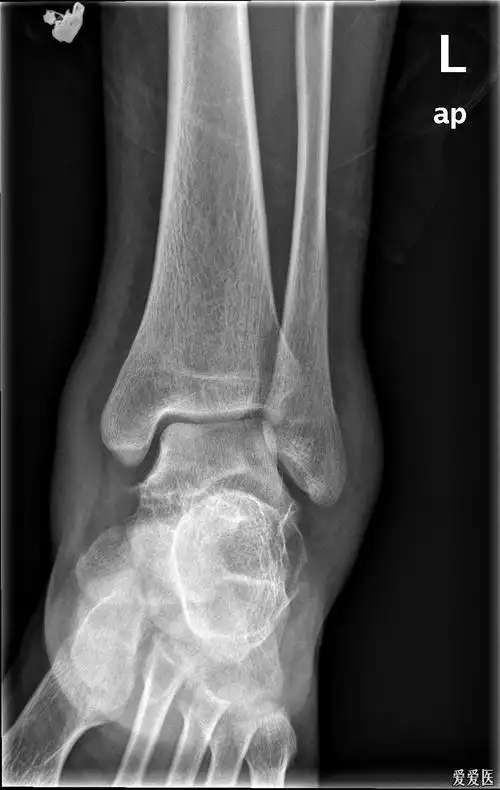

踝关节,正位和侧位x线照片

左距骨骨折_1002_1001.jpg